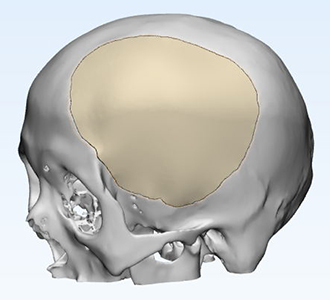

術(shù)前設(shè)計(jì)方案討論

因患者缺損部位存在腦組織塌陷,皮膚張力可能存在不足,因此給予建議略微降低修補(bǔ)部位peek弧度;設(shè)計(jì)完成后請(qǐng)臨床醫(yī)生確認(rèn)設(shè)計(jì)方案。